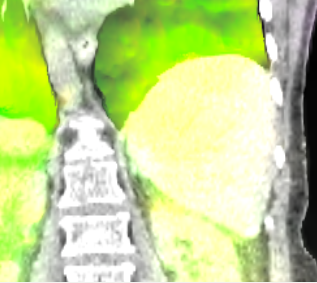

The mean DICE coefficients of the single-atlas registration of the liver and lung masks to the new static patient yield satisfying values of 0.860.12 and 0.960.09. Note the clearly different scan ranges of the data sets (Fig. 2a). The animation of the relevant structures is shown as an example in Fig. 3, using a variable real breathing signal of the target patient (Fig. 2b). In the puncture-relevant liver region, the patient’s breathing states are simulated plausibly for the 4D reference patient (Fig. 3) and, more importantly, the 3D patient (Figs. 4, 5), to which the motion model of was transferred333Demo movie, click here.

We achieve qualitatively plausible results for the liver area in this feasibility study. In the upper thorax especially at the rib cage in neighborhood to the dark lungs stronger artifacts can occur (Fig. 5c). They are due to problems in the inter-patient registration that is a necessary step for the transfer of the motion model. The non-linear deformation sometimes is prone to misaligned ribs. The same is true for the lower thorax with perforation first of the liver and then diaphragm (Fig. 4c). Further optimization have to be carried out as artifacts can appear on the high contrast lung edge (diaphragm, ribs) with a small tidal volume. For liver punctures only, the artifacts of smeared ribs are minor as can be seen in Fig. 4.